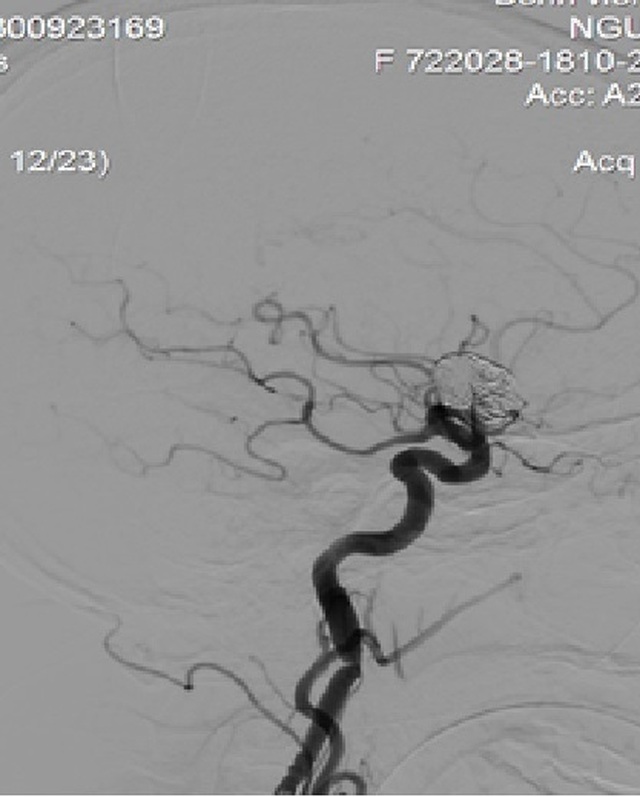

Stent chuyển dòng đặt vào động mạch cảnh trong phải phủ qua cổ túi phình khổng lồ

Nhờ quá trình can thiệp thành công, stent chuyển dòng phủ tốt cổ túi phình sau khi đã nút túi phình một phần bằng các vòng xoắn kim loại. Dòng chảy vào túi phình đã giảm đáng kể sau đặt stent chuyển hướng dòng chảy, làm giảm đến mức thấp nhất nguy cơ vỡ túi phình, cứu sống bệnh nhân.